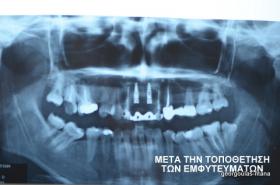

Στην ασθενή αυτή είχαν πραγματοποιηθεί 2 ενδοδοντικές θεραπείες (απονευρώσεις) που ακολουθήθηκαν από 2 ακρορριζεκτομές χωρίς επιτυχία. Η ασθενής ήταν δυσαρεστημένη με την όψη κ το χρώμα των δύο δοντιών και φυσικά με το πρόβλημα υγείας που δημιουργήθηκε. Πραγματοποιήθηκε εξαγωγή των δύο δοντιών, οστική αύξηση και τοποθέτηση 2 εμφυτευμάτων στις θέσεις των δύο κεντρικών τομέων. Τα δύο εμφυτεύματα αποκαταστάθηκαν με 2 υβριδικά κολοβώματα από διπυριτικό λίθιο και ολοκεραμικές στεφάνες ενώ στους 2 πλάγιους τομείς τοποθετήθηκαν επίσης ολοκεραμικές στεφάνες.